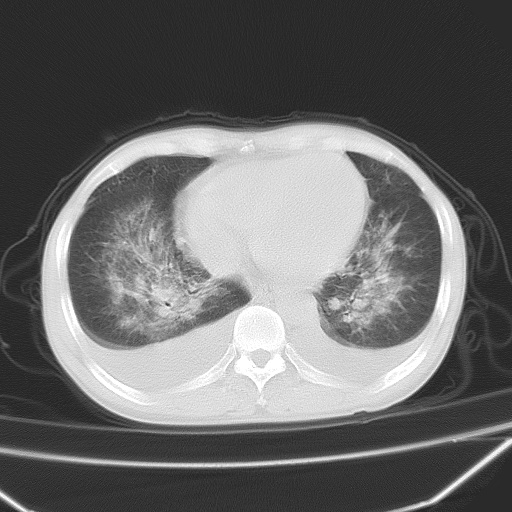

男、42岁、咯血3天。既往有甲亢、贫血、血尿蛋白尿史多年。血象:wbc:6.   中性粒:70.6%。

双肺野对称性磨玻璃影,分布于内中带,双侧胸水,患者有咯血。

双肺野广泛对称性磨玻璃影、实变影,以肺门为中心,主要分布于内中带,符合典型肺泡性肺水肿;伴双侧胸腔少量游离积液。结合患者既往病史且咯血就诊,支持多因素(尿毒症等)所致之肺水肿、肺出血、胸水;影像表现暂不考虑心源性水肿,且症状也不太符。需密切随诊结合临床治疗等进一步明确。